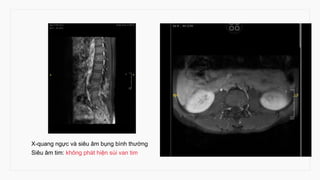

X-quang ngực và siêu âm bụng bình thường

Siêu âm tim: không phát hiện sùi van tim